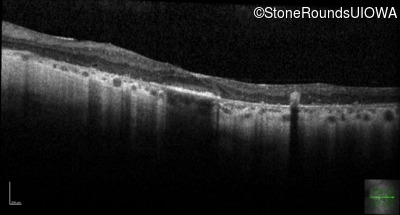

Optical Coherence Tomography - Right - 20/70

Exemplar / OCT Stack